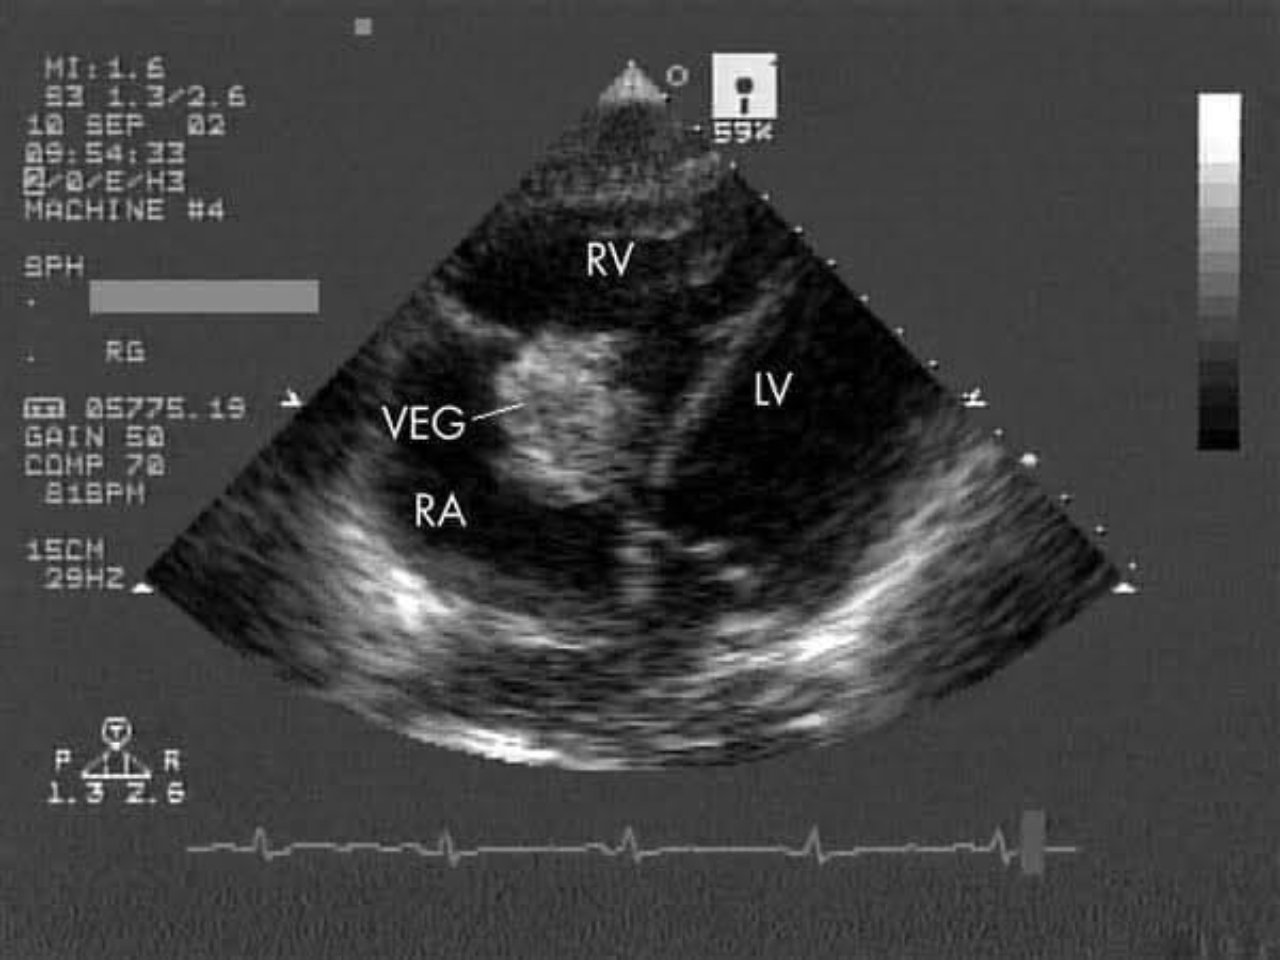

เคสเด็กญี่ปุ่น 4 ขวบ เป็นไข้มา 2 เดือน หาสาเหตุมาตลอดก็ไม่เจอ ให้ยาฆ่าเชื้อไป บางทีก็เหมือนไข้ลง พอให้จนครบแล้ว ไข้ก็เด้งกลับมาต่อ เลยหาจุดติดเชื้อในร่างกายยกใหญ่ แพทย์ใช้เครื่องเอคโค่ (Echocardiogram) ตรวจหัวใจ จึงตรวจพบก้อนโคโลนีเชื้อ (Vegetation) ที่ลิ้นหัวใจ tricuspid เพาะเชื้อขึ้นเป็นเชื้อ Streptococcus mutans ซึ่งเป็นเชื้อที่พบได้ในช่องปาก พอไปตรวจปาก ก็เจอฟันผุพอดี ซึ่งเป็นค่อนข้างเยอะด้วย

และเมื่อมันเกาะได้แล้ว มันจะเริ่มเพิ่มจำนวน กลายเป็นแหล่งที่อยู่ใหม่ของมัน กลายเป็นก้อนๆ เกาะตามตำแหน่งของหัวใจ เช่น ตามลิ้นหัวใจ, ตามผนัง กลายเป็นก้อนที่เรียกว่า Vegetation เรียกภาวะนี้ว่า ผนังหัวใจชั้นในติดเชื้อ (Infective endocarditis)